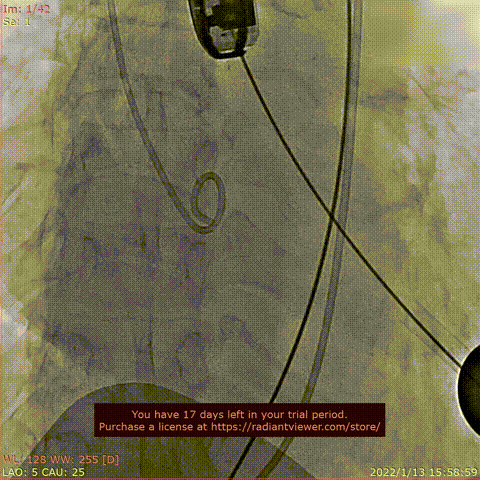

患者为68岁男性,因“胸闷、气促4余年,加重一年”主诉入院。术前超声心动图提示:左心增大,左室为著,左室壁肥厚,LVDD90 mm,LVEF35%,主动脉瓣右冠瓣脱垂、重度反流。术后即刻主动脉瓣大量反流消失,LVDD缩小至84 mm,左室较术前明显缩小。

术前DSA造影

瓣膜释放过程